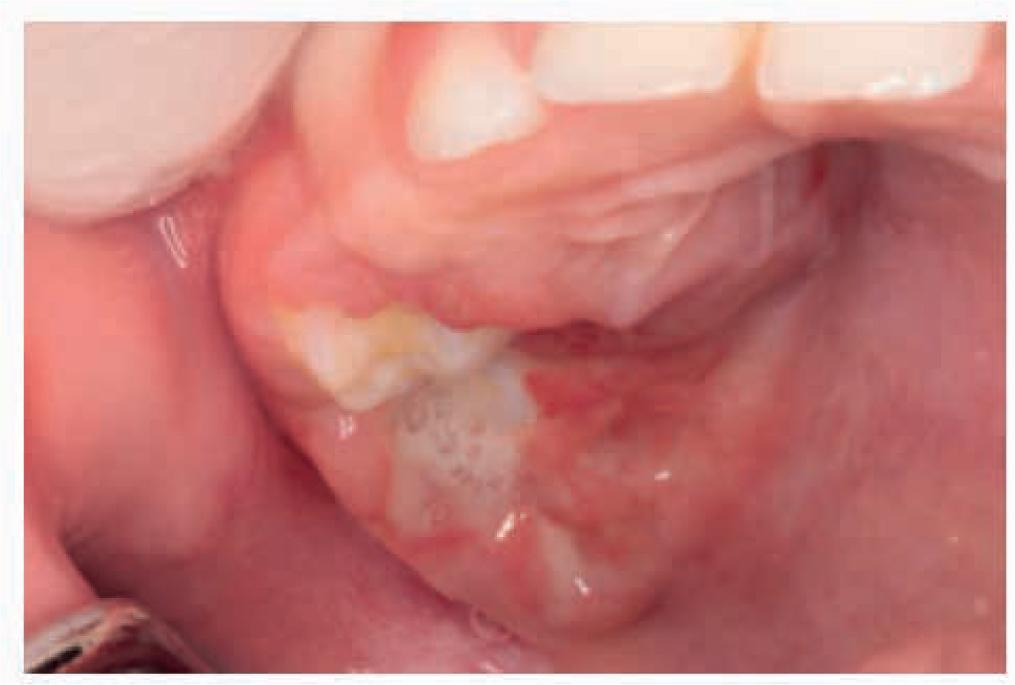

Medical records of 43 out of 44 patients with Langerhans cell histiocytosis were included in the study. One patient was excluded from the study due to the lack of dental examination as part of the diagnostic process. Age at diagnosis ranged between 0.33 and 16.33 years (mean 5.95 ± 4.66 years). Study group characteristics, including age at LCH diagnosis, sex, clinical form of LCH, as well as organs and systems involved, is presented in the form of a table (Tab. 1). Of 34 cases of single-system LCH, 31 (91.2%) involved bones, and 3 involved the skin (7.8%). Multisystem LCH most often involved the skin (8/9), followed by the bones (7/9) and lungs (5/9). Bone manifestations usually occurred in the craniofacial region (n = 23), including the skull (n = 11), mandible/maxilla (n = 7), orbit (n = 6), and zygomatic bone (n = 1). Less common locations included the spine (n = 8), long bones (n = 7), pelvis (n = 2), clavicle (n = 2) and ribs (n = 1). Diabetes insipidus (DI) was reported for four patients. Oral lesions in the form of gingivitis, pathological tooth mobility or expansion of the alveolar mandibular bone were observed in seven patients (Table 2, Figures 1–3). One patient was diagnosed with LCH based on histopathology of a gingival biopsy specimen.

| 5 | 1.44 | female | M-S | ulcer-like palatal lesions in the region of molars, root exposure and loosening of teeth 74, 75 | bilaterally involved palate in the region of molars and the alveolar part of the mandible | none | skull bones, orbit, lungs |

A 1,5 -year -old patient. Ulcer-like palatal lesions in the region of molars in the multi-system LCH